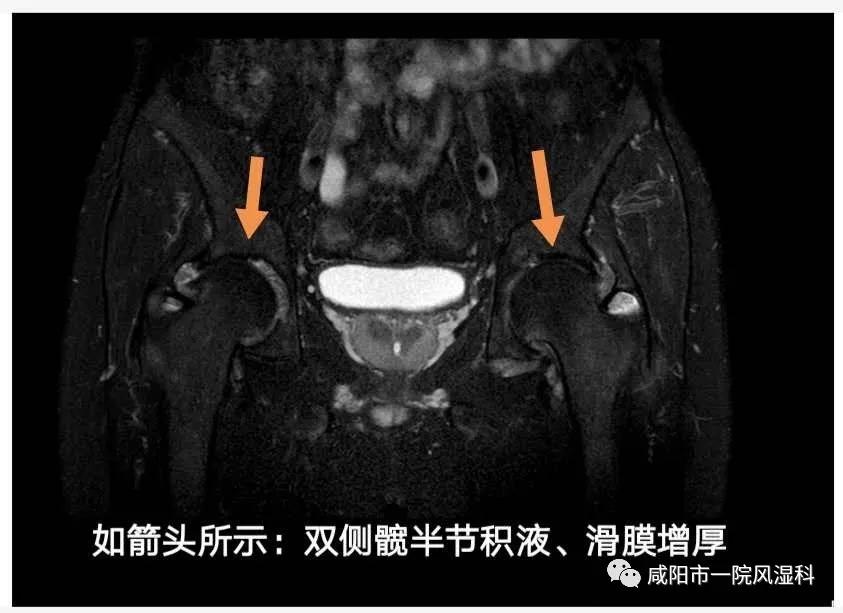

(四)外周关节:双侧髋关节受累。